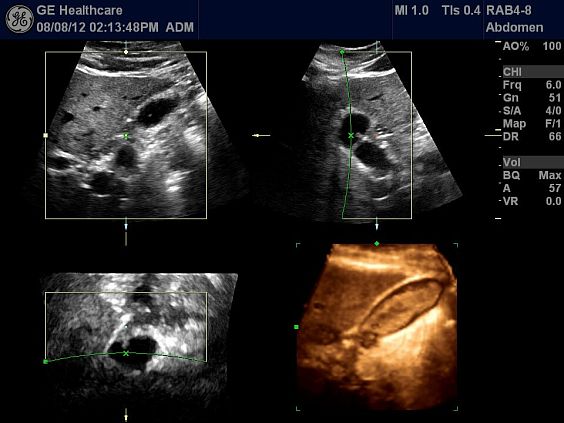

Клинические изображения

- Tomographic Ultrasound Imaging (TUI) - программа получения томографических срезов объемного ультразвукового изображения

- VOCAL II (Volume Calculation) - программа автоматических расчётов объема при использовании 3D/4D

- VCI Static (Volume Contrast Imaging) - режим объёмного контрастного изображения

- OmniView - режим улучшенной визуализации в любой проекции

- Режим 4D - трехмерное сканирование в режиме реального времени. Включает режим инверсии, Кинопетлю 4D и 3D в режиме ЦДК. Необходимы 4D датчики.

Ультразвуковой аппарат LOGIQ S7 XDclear предназначен для использования специалистами из различных областей диагностики. Его расширенный функционал включает такие возможности как B-Flow — недопплеровская технология отображения кровотока в B-режиме, компрессионная эластография (качественная и полуколичественная), количественный анализ васкуляризации, функцию В-Steer+ — изменение угла наклона УЗ луча в B-режиме, 3D/4D диагностику и мультимодальную визуализацию.